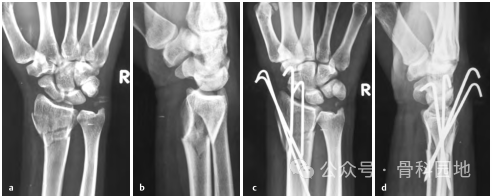

9、桡骨茎突骨折伴背侧移位,复位后,用两根桡骨茎突克氏针固定:一根位于背侧,另一根位于掌侧至茎突尖端。(下图a、b)

10、桡骨远端四部分骨折,向背侧移位,月骨窝骨块与掌侧移位分离。可以克氏针从背皮质以倾斜方式从近端到远端掌骨骨块固定。(下图a,b)。